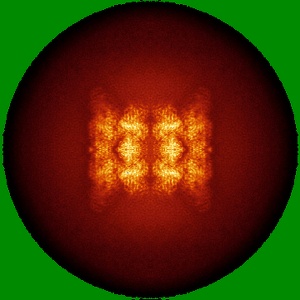

Human p97/VCP structure with a triazole inhibitor (NSC799462/dodecamer)

Single-particle3.33 Å

Sample: p97/VCP AAA+ ATPase/NSC799462

Mechanism of allosteric inhibition of human p97/VCP ATPase and its disease mutant by triazole inhibitors.

(2024) Commun Chem , 7 , 177 - 177